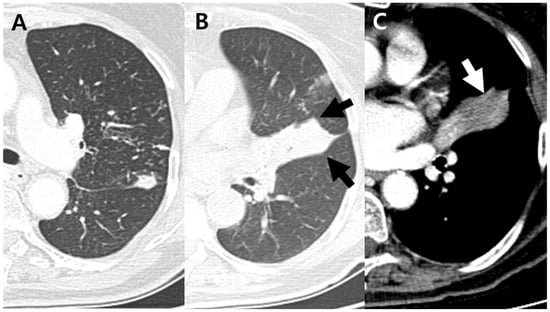

Figure 3.

A 75-year-old woman with pulmonary tuberculosis and underlying bronchial anthracofibrosis presented with cough and sputum. (A) Axial CT scan showed clustered micronodules and consolidations in left upper lobe. These findings were well known typical CT findings of pulmonary tuberculosis. (B,C) Axial CT scan showed complete obstruction of lingular divisional bronchus, resulting in atelectasis with focal contour bulge (black arrows) and internal low-density area (white arrow). These findings were atypical CT findings of pulmonary tuberculosis, which cannot be suspected of TB. CT = computed tomography.